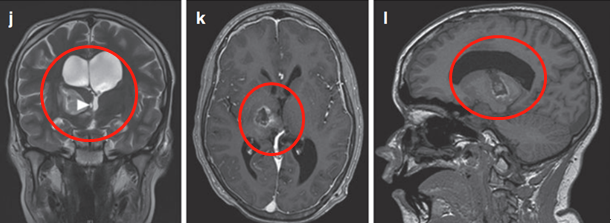

(圖6a、b)軸位MRI造影劑及冠狀面T2-WI顯示一個(gè)環(huán)形增強(qiáng)的右側(cè)丘腦結(jié)節(jié)腫瘤。

丘腦膠質(zhì)瘤

圖6

腫瘤累及內(nèi)側(cè)顳結(jié)構(gòu)(圖6c),Rutka教授考慮根據(jù)其病情進(jìn)展制定綜合治療方案,先行經(jīng)顳中回經(jīng)腦室入路次全切除腫瘤,組織學(xué)為WHO I級(jí)毛細(xì)胞星形細(xì)胞瘤,BRAF重復(fù)融合狀態(tài)為陰性。免疫組化檢測(cè)BRAF V600E、H3K27M陰性。基因測(cè)試證實(shí)了NF1基因的變異。術(shù)后嚴(yán)密隨訪患兒術(shù)后情況。